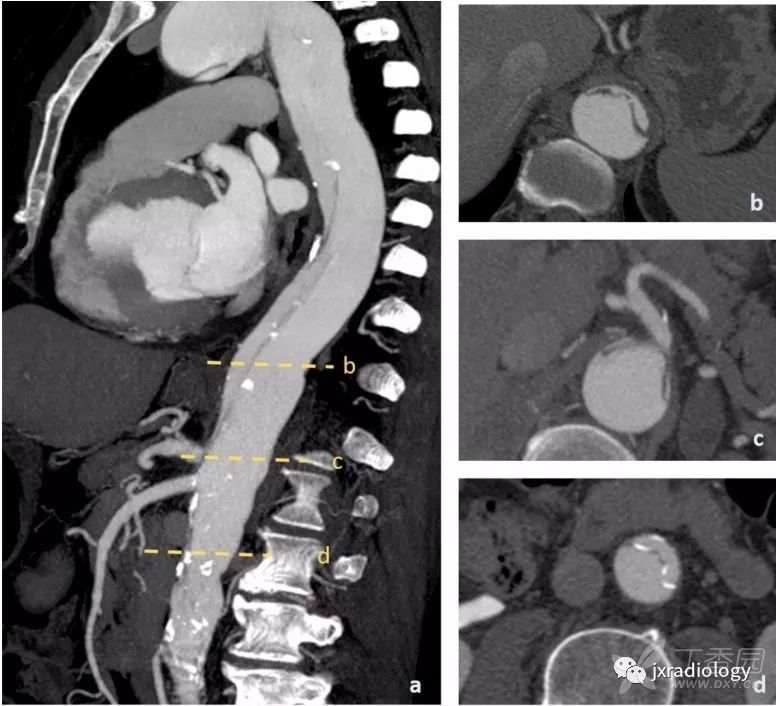

图18:增强后CT显示主动脉夹层Stanford B型(内膜瓣不延伸到左锁骨下动脉的开口处 a和e)。

腹腔干、肠系膜上动脉从真腔中开口(b图星号),以及左肾动脉(c图星号),右肾动脉从假腔开口。 夹层延伸超过主动脉分叉累及髂总动脉。